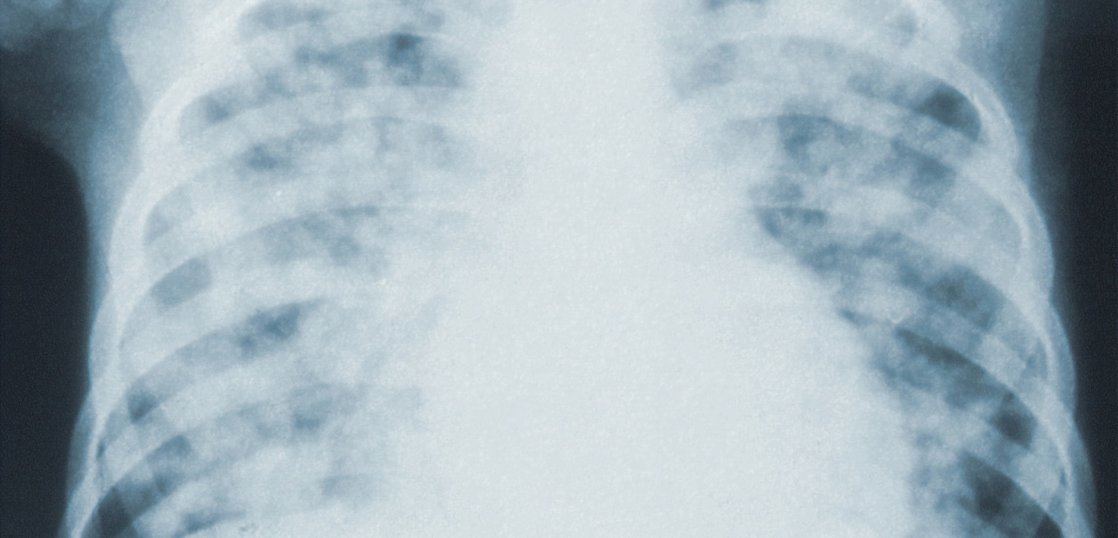

中国国務院(政府)は24日、学校や病院で呼吸器疾患が急増する中、国内に警戒を呼びかけた。

インフルエンザがこの冬から春にかけてピークを迎え、マイコプラズマ肺炎は今後も一部地域で高い感染水準が続くと指摘。

また、新型コロナウイルス感染症の再拡大リスクにも警鐘を鳴らした。